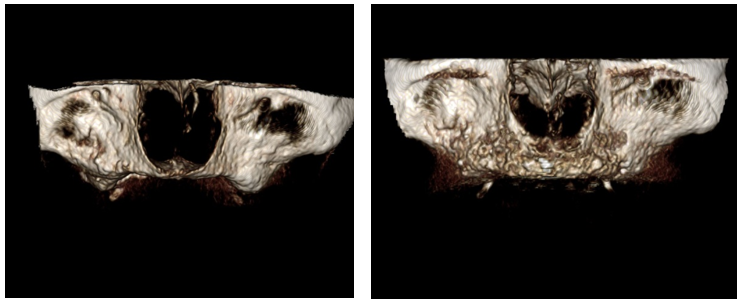

Figure 8 (a & b). Pre op 3-D reconstruction (left) and post op(right) demonstrating increased ridge thickness after grafting.

Figure 8 (c & d). Pre op (left) post op(right) demonstrating increased vertical bone height. This technique predictably produces the height planned.

Figure 1. 62-year-old female with Class V ridge. Redundant flabby tissue on the ridge with little bone support and inability to wear a full denture. Patient underwent bilateral sinus lifts, vertical and horizontal ridge augmentation with a tissue engineering triad technique with PRP as the stem cell source. This patient was treated in the office.

Figure 2 (a & b). Pre op panorex (left) showing highly pneumatized sinus short anterior ridge height anterior. Post op (right) panorex with imaging guide, bilateral sinus lifts and vertical and horizontal ridge augmentation.

Figure 3 (a & b). Pre and post-operative sagittal cone beam views of ridge augmentation revealing excellent horizontal and vertical gains.